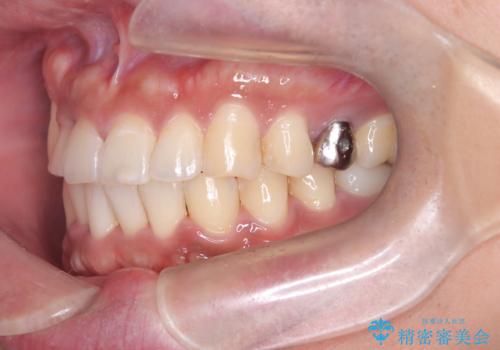

【ワイヤー矯正】八重歯と下の歯の凸凹を治したい

- 主訴:右上の八重歯と、下の歯の凸凹を治したい

上顎右側第一小臼歯と下顎右側第一小臼歯を抜歯しワイヤー矯正を行いました。

右側2級、左側1関係だったため、右側上下第一小臼歯を抜歯し、ワイヤー矯正を行いました。

期間:2年6カ月